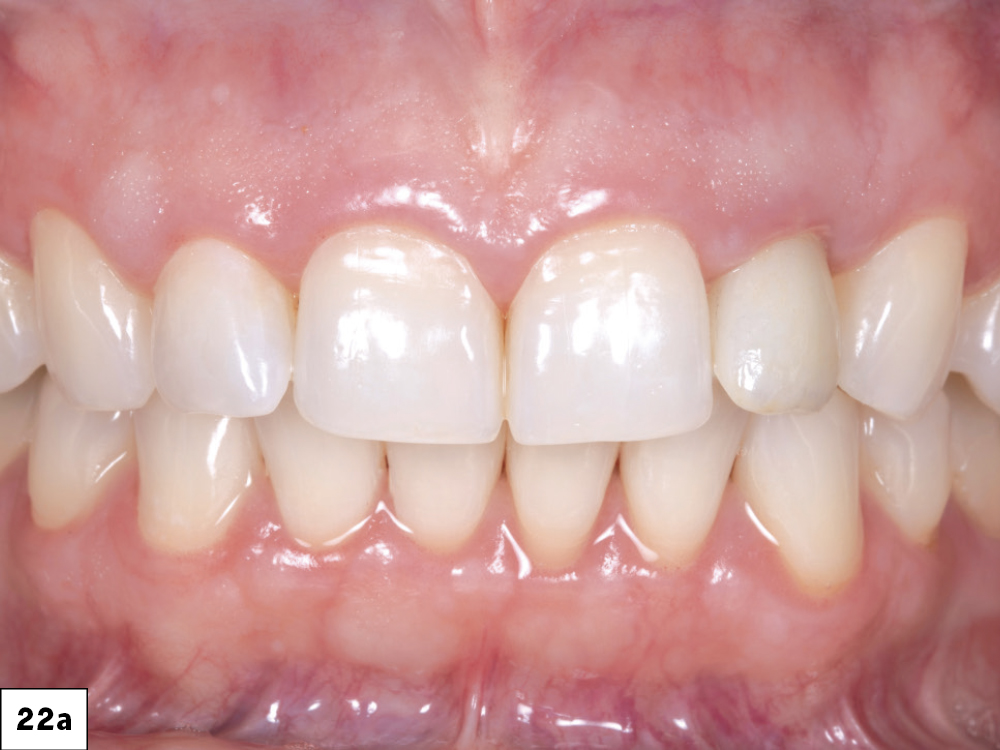

Upon first glance, the soft tissue and the teeth look acceptable.

Figure 1: Upon first glance, the soft tissue and the teeth look acceptable. However, the radiograph tells a different story (Fig 2). The patient stated that she had suffered facial trauma about seven years ago. Over time, the mobility of the upper left lateral incisor has increased.